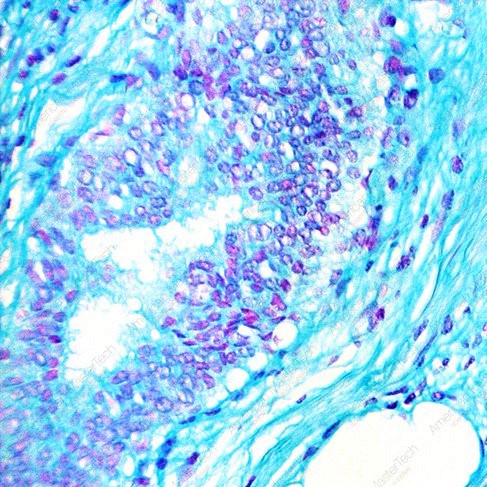

- La microespectrofotometría de Feulgen se basa en la capacidad de cuantificar la cantidad de ADN presente en una célula o núcleo celular específico. Esto se logra mediante la interacción del ADN con un reactivo llamado reactivo de Feulgen.

- El reactivo de Feulgen se une específicamente al ADN, formando complejos que pueden ser detectados y cuantificados con precisión mediante espectrofotometría. La cantidad de luz absorbida por estos complejos proporciona una medida directa del contenido de ADN.

- La microespectrofotometría de Feulgen se utiliza para determinar la ploidía de una célula o tejido al analizar la cantidad de ADN presente. Las células diploides normalmente tendrán el doble de contenido de ADN en comparación con las células haploides.